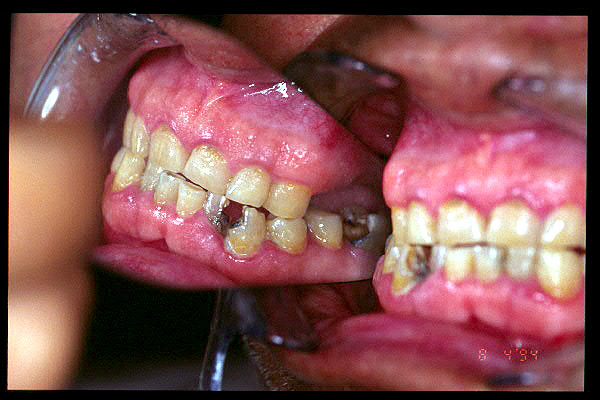

CM Desgaste por bruxismo, presencia de cálculo